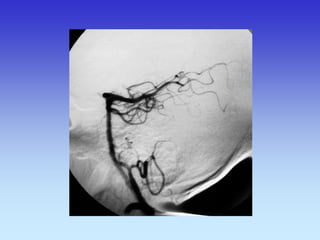

METODE PRIKAZA KRVNIH ŽILA

•UZ-DOPPLER

•DSA

•CTA

•MRA